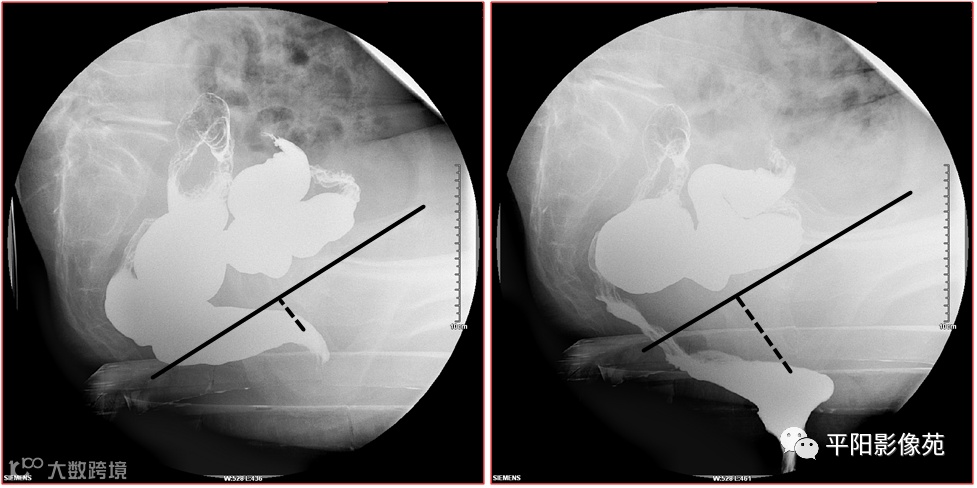

会阴下降(perineum descending,PD)是指用力排便时肛上距≥31mm(经产妇≥36mm)者。伴有其他异常时称之为会阴下降综合征(descending perineum syndrome,DPS)。(图1)

图1 力排时肛上距明显增大>31mm